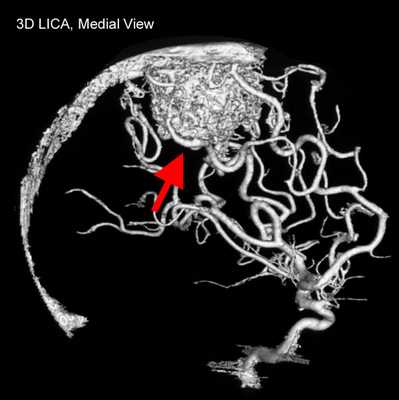

Как выглядит АВМ на КТ. Артерио-венозная мальформация - врожденная патология, выглядящая на КТ как «клубок» извитых и неравномерно расширенных артерий и вен. Может содержать обызвествления и тромбы. Возможен также смешанный вариант - лимфатико-вено-артериальная мальформация.

![]()